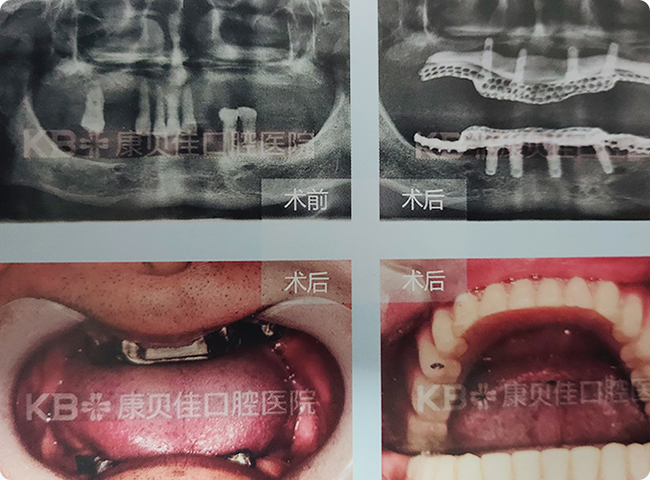

近10余年来由于牙体及牙周疾病,多颗牙陆续脱落或拔除,口内余留牙为数不多。有多年活动义齿佩戴史,对活动义齿的固位、咀囑效率、舒适度均不满意,因此要求种植固定修复。修复方案设计为上颌行双侧上颌窦外提升术后延期植入4颗种植体,下颌植入4颗种植体,杆卡修复全口牙。

口内大部分牙齿缺失,影响进食,由于看到老伴用的活动假牙,每天取上取下,而且吃东西费劲,有时候还会磨出溃疡很痛苦,所以强烈要求固定式修复。康贝佳口腔种植科专家在其上颌植入4颗种植体并用杆卡辅助义齿修复,术后恢复效果好,咀嚼效率大大提高。